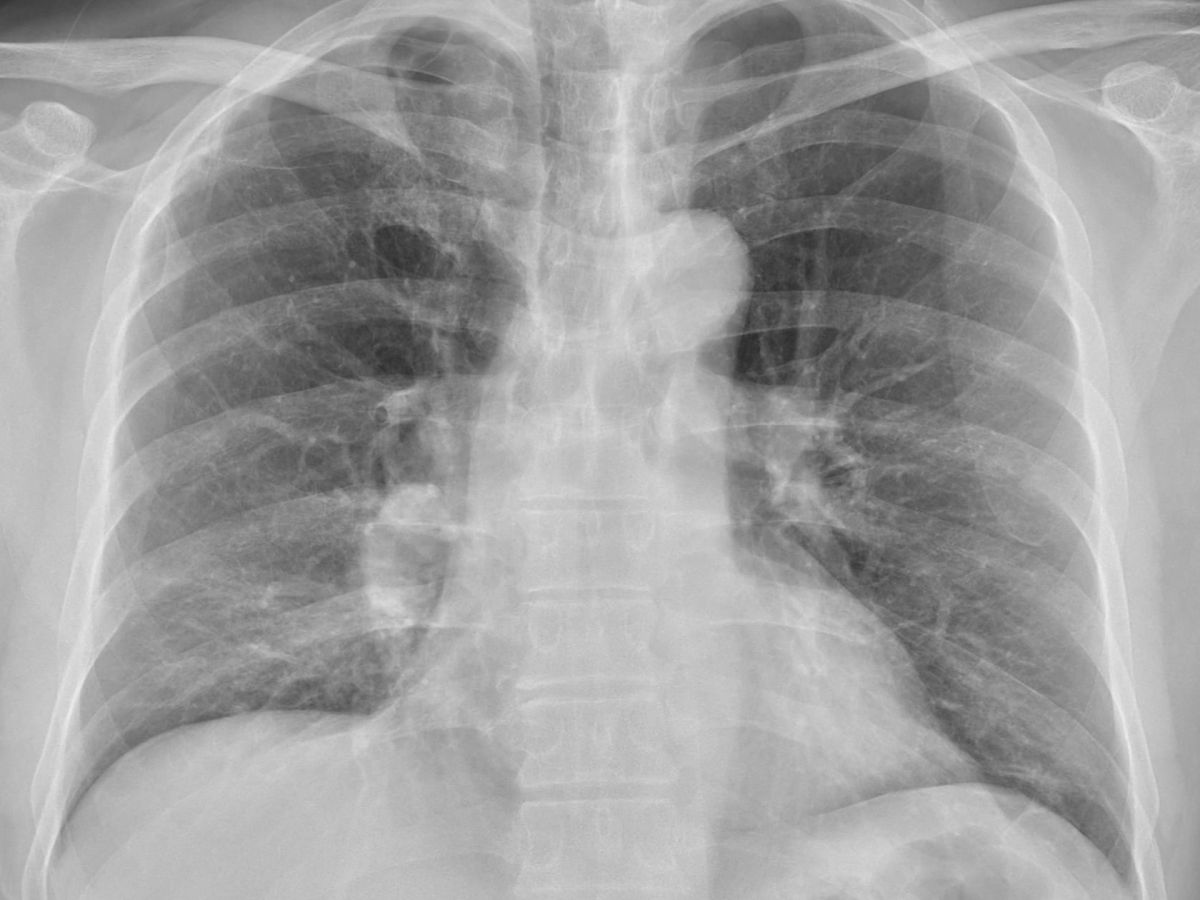

▲蘇一峰圈出肺癌位置(紅圈處),感嘆「這個X光要發現肺癌真的很難」。(圖/翻攝蘇一峰臉書) 貼文一出引發討論,醫師潘建志也留言「我看不出來,丟給AI,也看不出來。(不慌不慌,還有人類放射科醫師。)」,蘇一峰回說「其實這張X光,放射科醫師也沒看出來」,並以紅圈標示出肺癌位置。

胸腔科醫師蘇一峰昨(17)在臉書分享,「40幾歲男性,只是咳嗽一個月而已...」,未料經影像檢查發現,他已肺癌末期且合併其他器官轉移,患者一度無法接受,哭喊「我不相信!我要帶資料再多問幾家醫院!」蘇一峰補充說,「話說這個X光要發現肺癌真的很難...」,並說患者癌細胞已轉移至腎上腺。